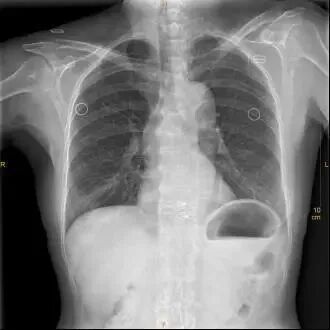

④这已经不只是文胸的问题,外套都没脱。

X光拍片为什么要等【影像科普】拍片为什么会要求脱衣服?_https://www.jmylbn.com_新闻资讯_第7张